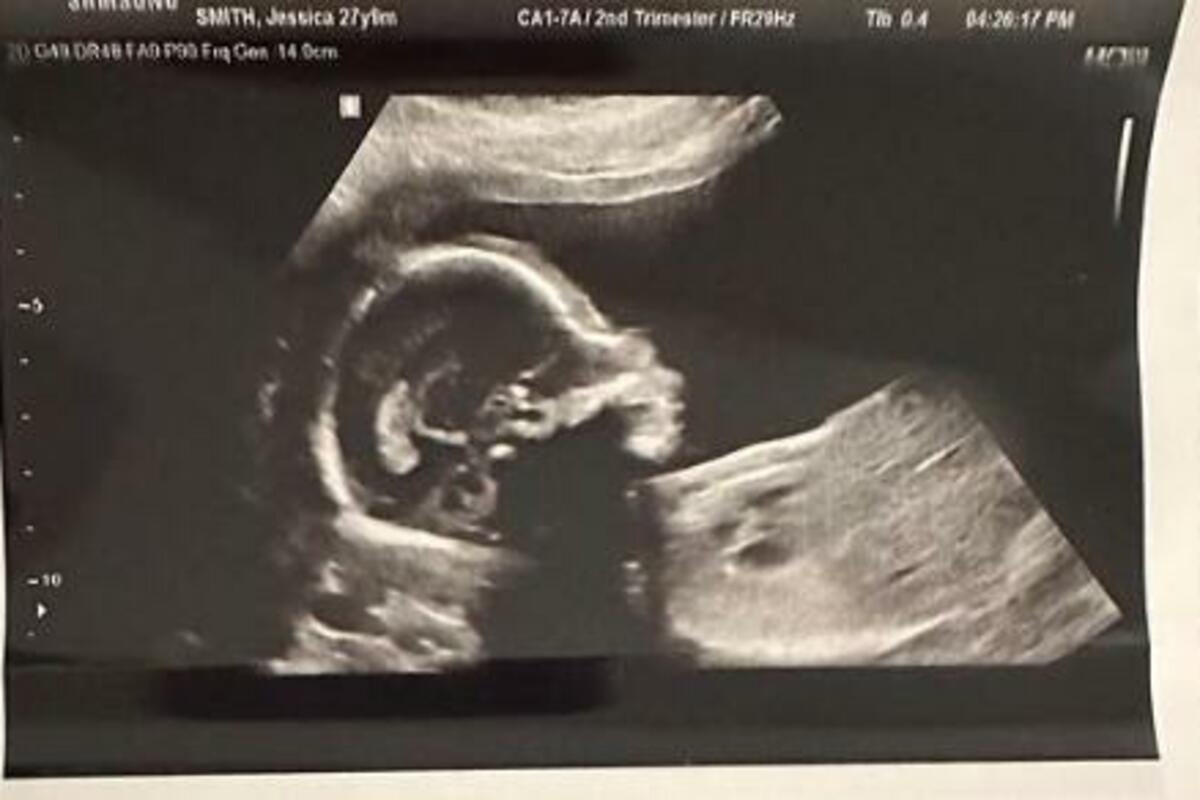

- Devojka i ja pokušavali smo dugo da dobijemo dete. Pa je tako, kada je ostala trudna prva poseta doktoru trebala da bude sjajna stvar. Međutim kada sam na ekranu video datum začeća, bio sam skrhan - napisao je jedan čovek.

Ona je, naime, imala aferu samo nekoliko dana od njihovog zadnjeg odnosa a ultrazvuk je pokazao da je otac zapravo njen ljubavnik.

-Ultrazvuk daje indikaciju začeća, a samim tim i verovatan datum rođenja na osnovu datuma poslednje menstruacije žene. Ali jedini način da se sa sigurnošću sazna ko je otac je da uradite DNK test nakon što se dete rodi. Što se tiče vaše veze, ako ste bili srećni pre i posle ovog privremenog razdvajanja, verovatno možete da učinite da vaša veza funkcioniše. Ali morate da naučite da bolje komunicirate zajedno.